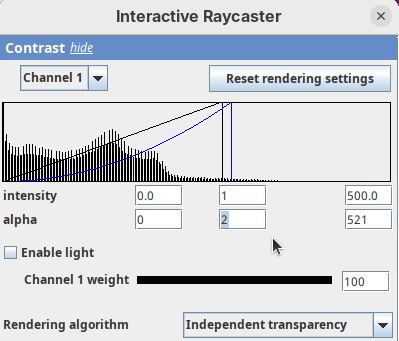

- Set it to

0.

By default 3Dscript sets the gamma value of alpha to 2.0. That’s a good default for fluorescence microscopy (see the next dataset below), but since this is MRI data, we need to tweak it a little differently.

- Set the alpha gamma value to

1.0.

Note that this improves the visualization as the head’s surface becomes better visible.

- Now set the alpha

maxto250.

The surface will become even more solid because we are defining that pixels that have a value above 250 will be fully opaque.

- To compare, set alpha

maxto5000.

You will notice that the sample will become more transparent. Even the brain inside the skull will be visible.

- Set alpha

maxback to500.

Generally, setting the intensity and alpha to the same values is a good starting point for optimizing the rendering.